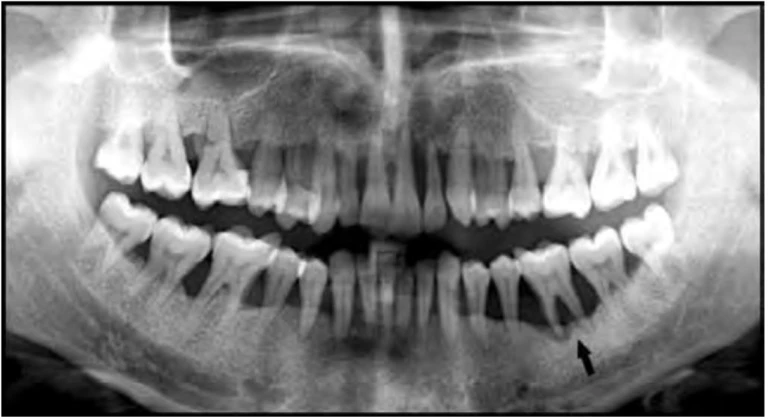

Hình 9F. Mũi tên đen chỉ răng cối lớn thứ nhất hàm dưới được chỉ định nhổ vì tình trạng nha chu